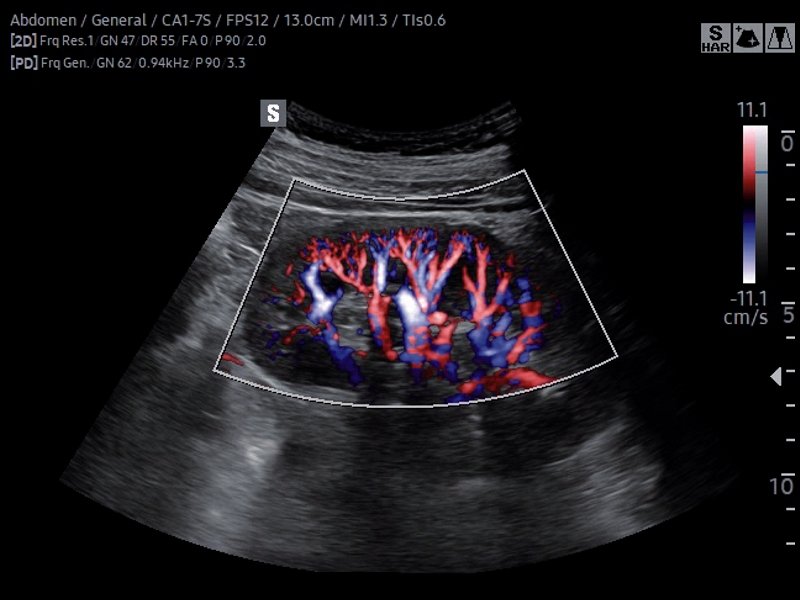

Kidney, S-Flow (echogramm №816)

[RU] Ultrasound image №816: Kidney in S-Flow™ mode (convex probe 1-7 MHz).

Echogramm was received by ultrasound scanner RS85 (available for sale).